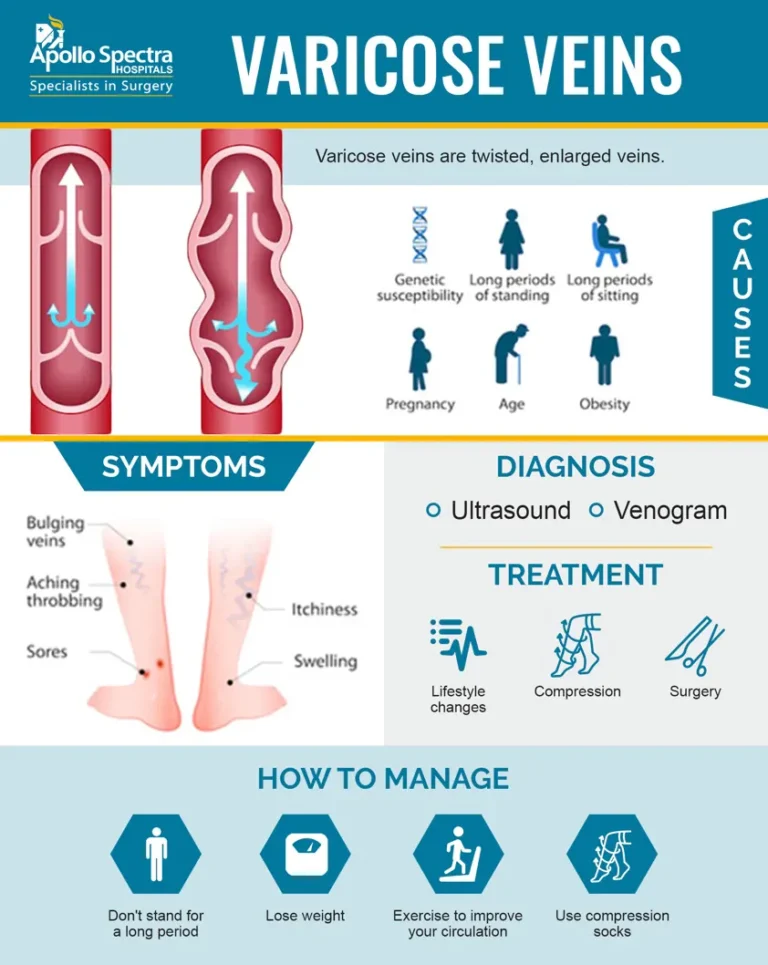

Venous insufficiency is a condition in which the valves inside the leg veins become weak or damaged, allowing blood to flow backward and pool instead of returning efficiently to the heart. This leads to increased pressure in the veins and causes varicose veins—the twisted, bulging veins you often see on the legs.

Why Do Varicose Veins Form?

We explain veins like “one-way streets”—healthy veins carry blood upward, aided by valves. When those valves become leaky, blood flows in the wrong direction, builds up pressure, and stretches the veins, leading to varicosities.

Venous insufficiency often runs in families and may be worsened by:

- Prolonged standing or sitting

- Pregnancy

- Obesity

- Hormonal changes or aging

Evaluation and Conservative Management

We begin with a comprehensive vein ultrasound to map your vein anatomy, assess valve function, and locate reflux (backflow). If the condition is mild, we start with:

- Compression stockings